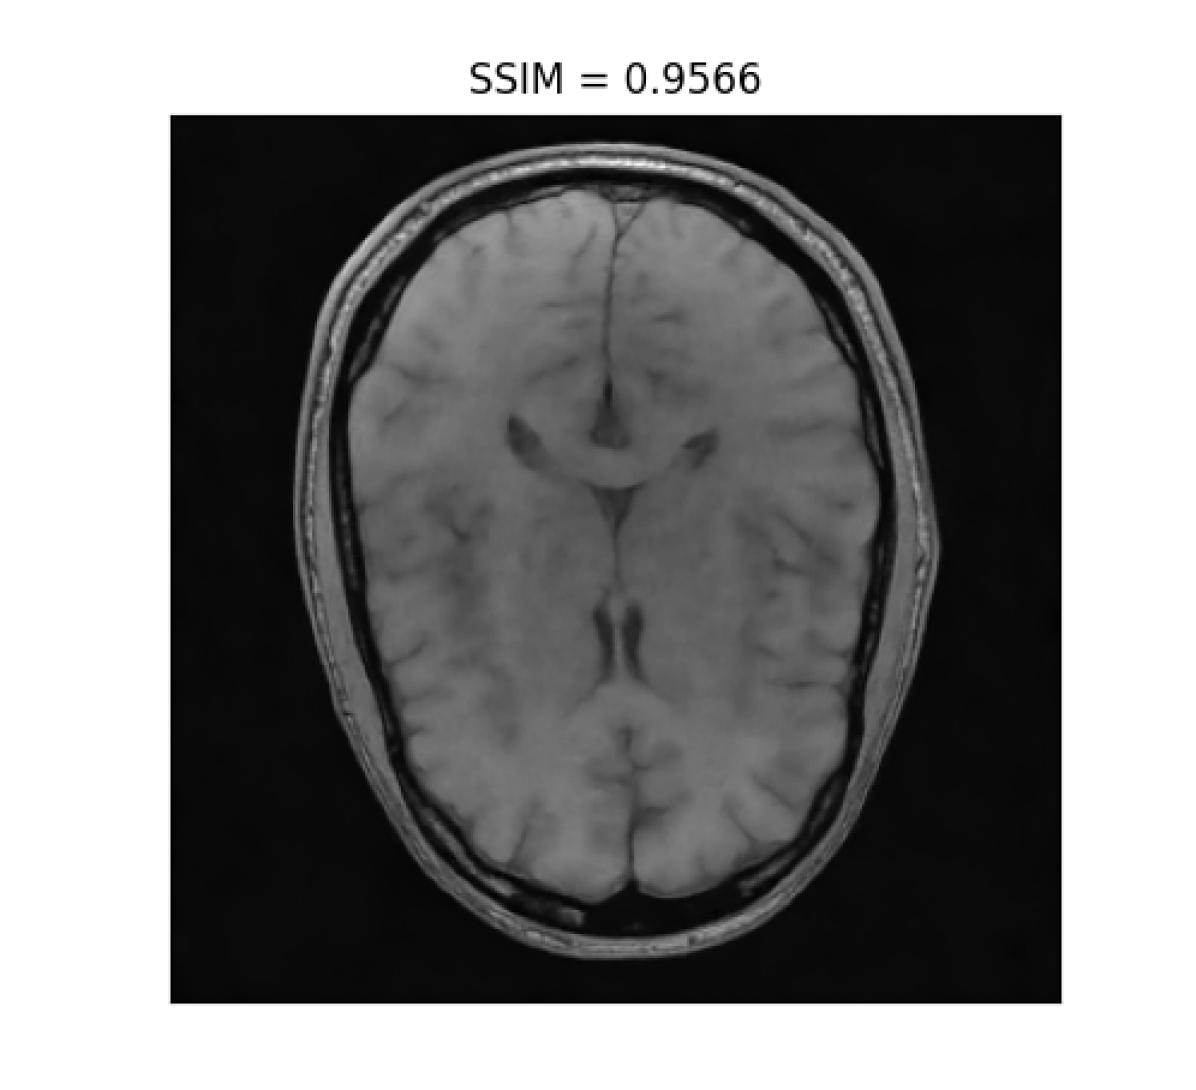

III-B2 Qualitative results

For visual inspection, we present the results of image reconstruction from data undersampled using SPARKLING trajectories generated for various target densities in Fig. 3 (T1subscriptT1\text{T}_{1}-w images) and Fig. 4 (T2subscriptT2\text{T}_{2}-w images). For the sake of space, we only report the best reconstruction results, i.e. with NC-PDNet. For T1subscriptT1\text{T}_{1}-weighted contrast, we show that all methods give similarly performing results, however 𝝆vdssubscript𝝆𝑣𝑑𝑠\boldsymbol{\rm\rho}_{vds} and 𝝆lbsubscript𝝆𝑙𝑏\boldsymbol{\rm\rho}_{lb} provide the best SSIM scores. Further, we observe that in this case, 𝝆vdssubscript𝝆𝑣𝑑𝑠\boldsymbol{\rm\rho}_{vds} is slightly better than 𝝆lbsubscript𝝆𝑙𝑏\boldsymbol{\rm\rho}_{lb}. On the contrary, for T2subscriptT2\text{T}_{2}-w contrast, 𝝆lbsubscript𝝆𝑙𝑏\boldsymbol{\rm\rho}_{lb} outperforms the other densities as reflected both visually in Fig. 4 and quantitatively (see Fig. 2).

Reference T1subscript𝑇1T_{1}-w Image (i) 𝝆vdssubscript𝝆𝑣𝑑𝑠\boldsymbol{\rm\rho}_{vds} (ii) 𝝆sbsubscript𝝆𝑠𝑏\boldsymbol{\rm\rho}_{sb} (iii) 𝝆lsbsubscript𝝆𝑙𝑠𝑏\boldsymbol{\rm\rho}_{lsb} (iii) 𝝆lbsubscript𝝆𝑙𝑏\boldsymbol{\rm\rho}_{lb}

Refer to caption Refer to caption Refer to caption Refer to caption Refer to caption

Figure 3: NC-PDNet-based image reconstruction for retrospective T1𝑇1T1-w imaging with slice 666 in file_brain_AXT1_201_6002725.h5 from validation data in fastMRI dataset for different target sampling densities.